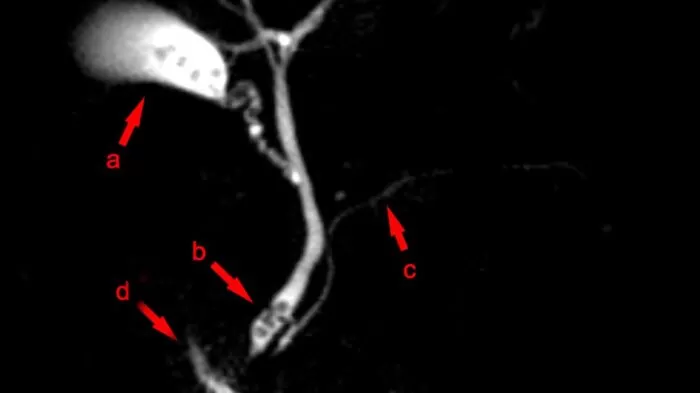

12. حصوات المرارة

- تتشكل حصوات المرارة عندما يكون هناك تركيز عالٍ من الصفراء أو البيليروبين أو الكوليسترول في السائل المخزن داخل المرارة

- لا تسبب حصوات المرارة عادةً أعراضًا أو ألمًا حتى تسد فتحة المرارة أو القنوات الصفراوية

- يحدث ألم في الجزء العلوي الأيمن من البطن أو ألم في المعدة بعد تناول الأطعمة التي تحتوي على نسبة عالية من الدهون

- تشمل الأعراض الأخرى الألم المصحوب بالغثيان والقيء والبول الداكن والبراز الأبيض والإسهال والتجشؤ وعسر الهضم

15. انسداد القناة الصفراوية

تعتبر هذه الحالة حالة طبية طارئة. قد تكون هناك حاجة إلى رعاية عاجلة.

- السبب الأكثر شيوعًا هو حصوات المرارة، ولكن قد يحدث أيضًا بسبب إصابة الكبد أو المرارة، أو الالتهاب، أو الأورام، أو العدوى، أو الخراجات، أو تلف الكبد

- اصفرار الجلد أو العينين، حكة شديدة في الجلد دون طفح جلدي، براز فاتح اللون، بول داكن جدًا

- ألم في الجانب الأيمن العلوي من البطن، غثيان، قيء، حمى

- يمكن أن يسبب الانسداد عدوى خطيرة تتطلب عناية طبية عاجلة